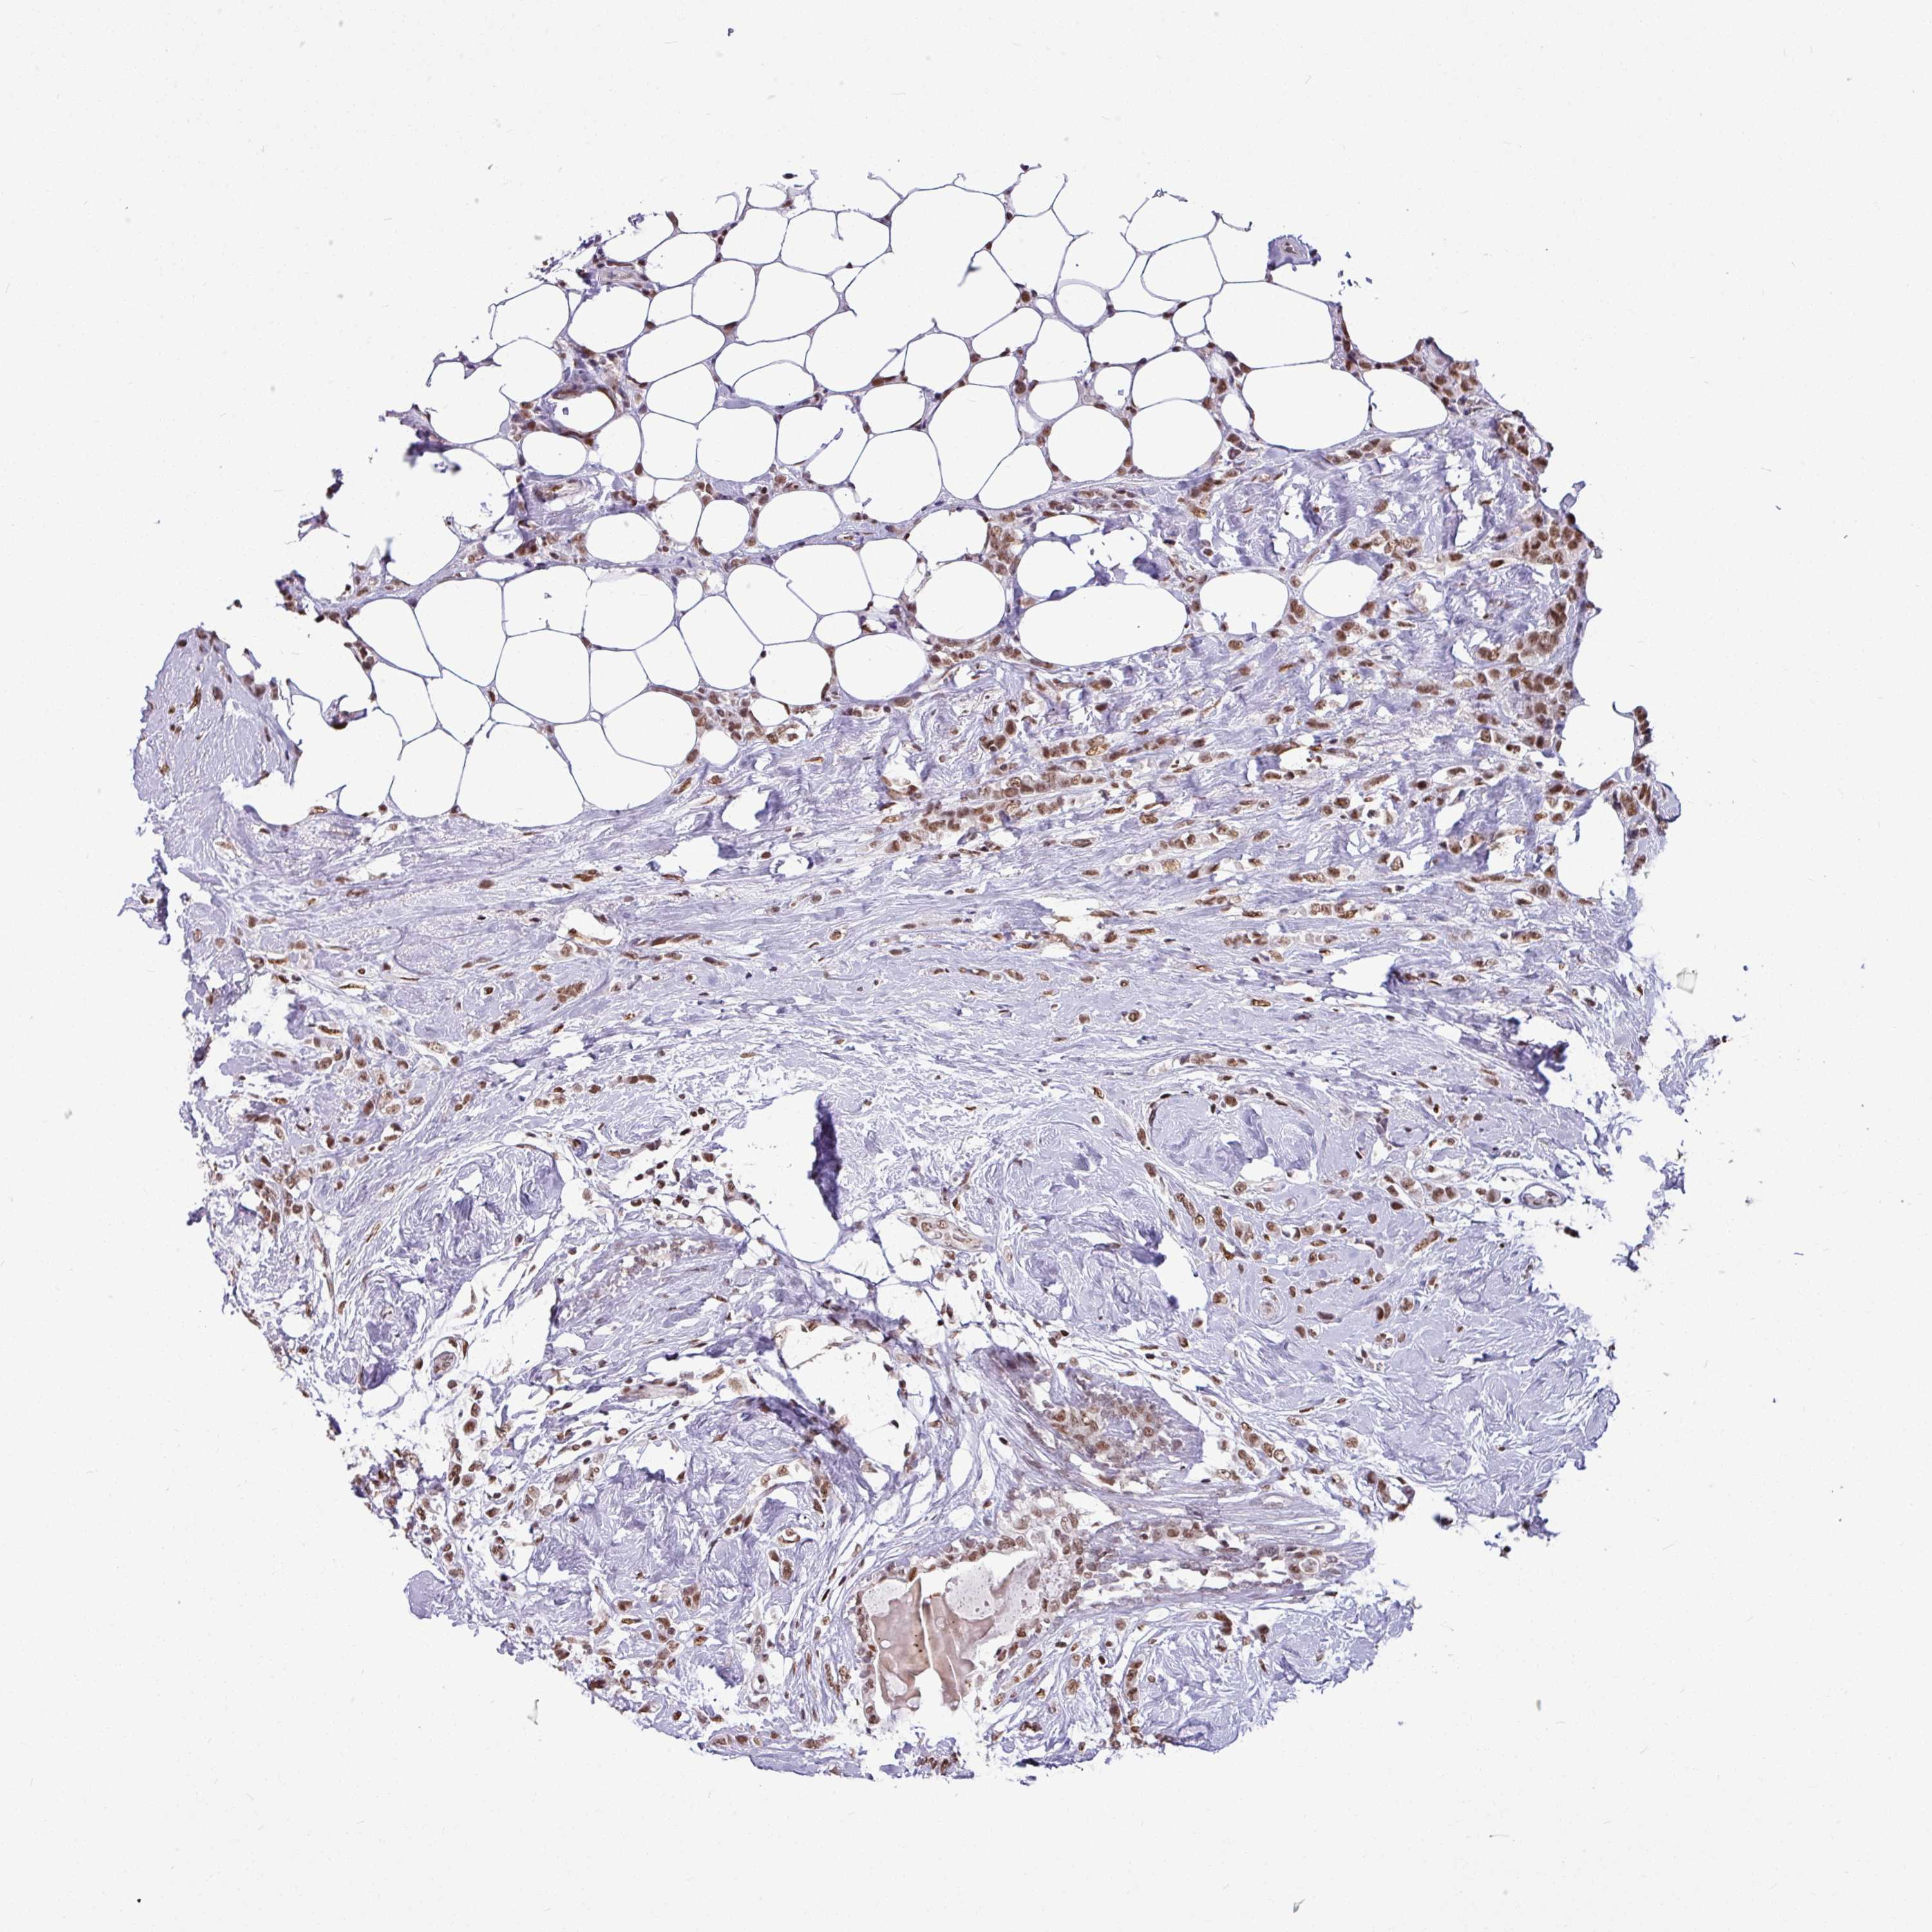

CANCER BREAST CANCER Show tissue menu

BRCA TCGA BRCA VALIDATION PROTEIN EXPRESSION